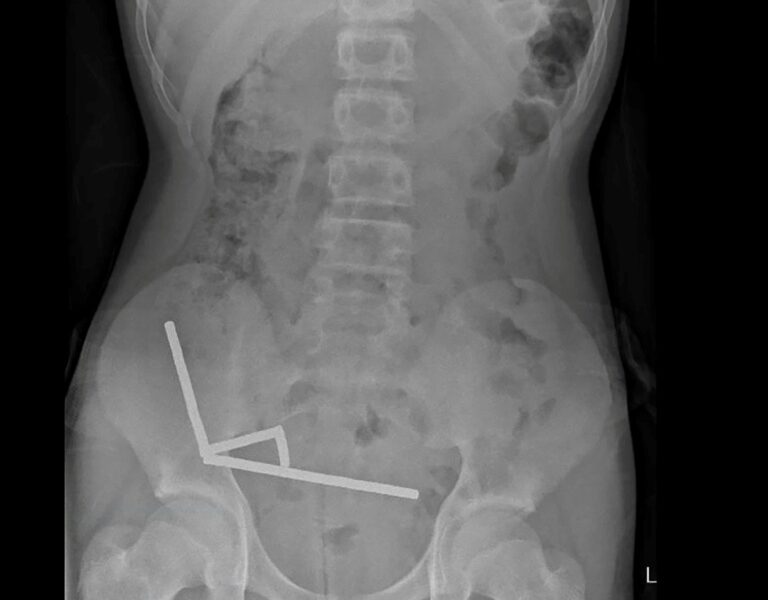

The introduction of SIR-Spheres represents a new approach to radioembolization, a procedure that combines radiation therapy with an embolization technique to target cancer cells directly. Dr. Mahvash highlighted key clinical findings that supported the approval, noting the effectiveness of Y-90 microspheres in delivering localized radiation while minimizing damage to surrounding healthy tissue.

The approval comes after rigorous clinical trials demonstrating the safety and efficacy of SIR-Spheres. These microspheres allow for precise targeting of tumor tissues, which can lead to improved patient outcomes. Dr. Mahvash pointed out that this treatment option could be particularly beneficial for patients with limited liver function who are often excluded from other therapies.